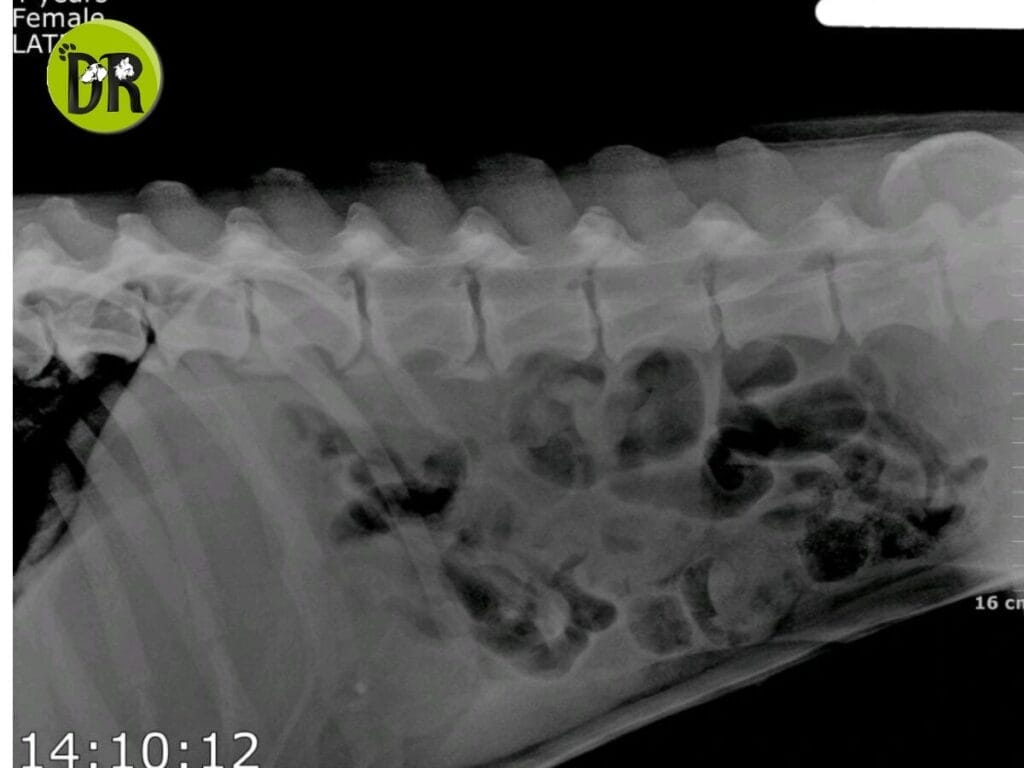

Radiography revealed intestinal loops filled with radiolucent gases, and plicated loops